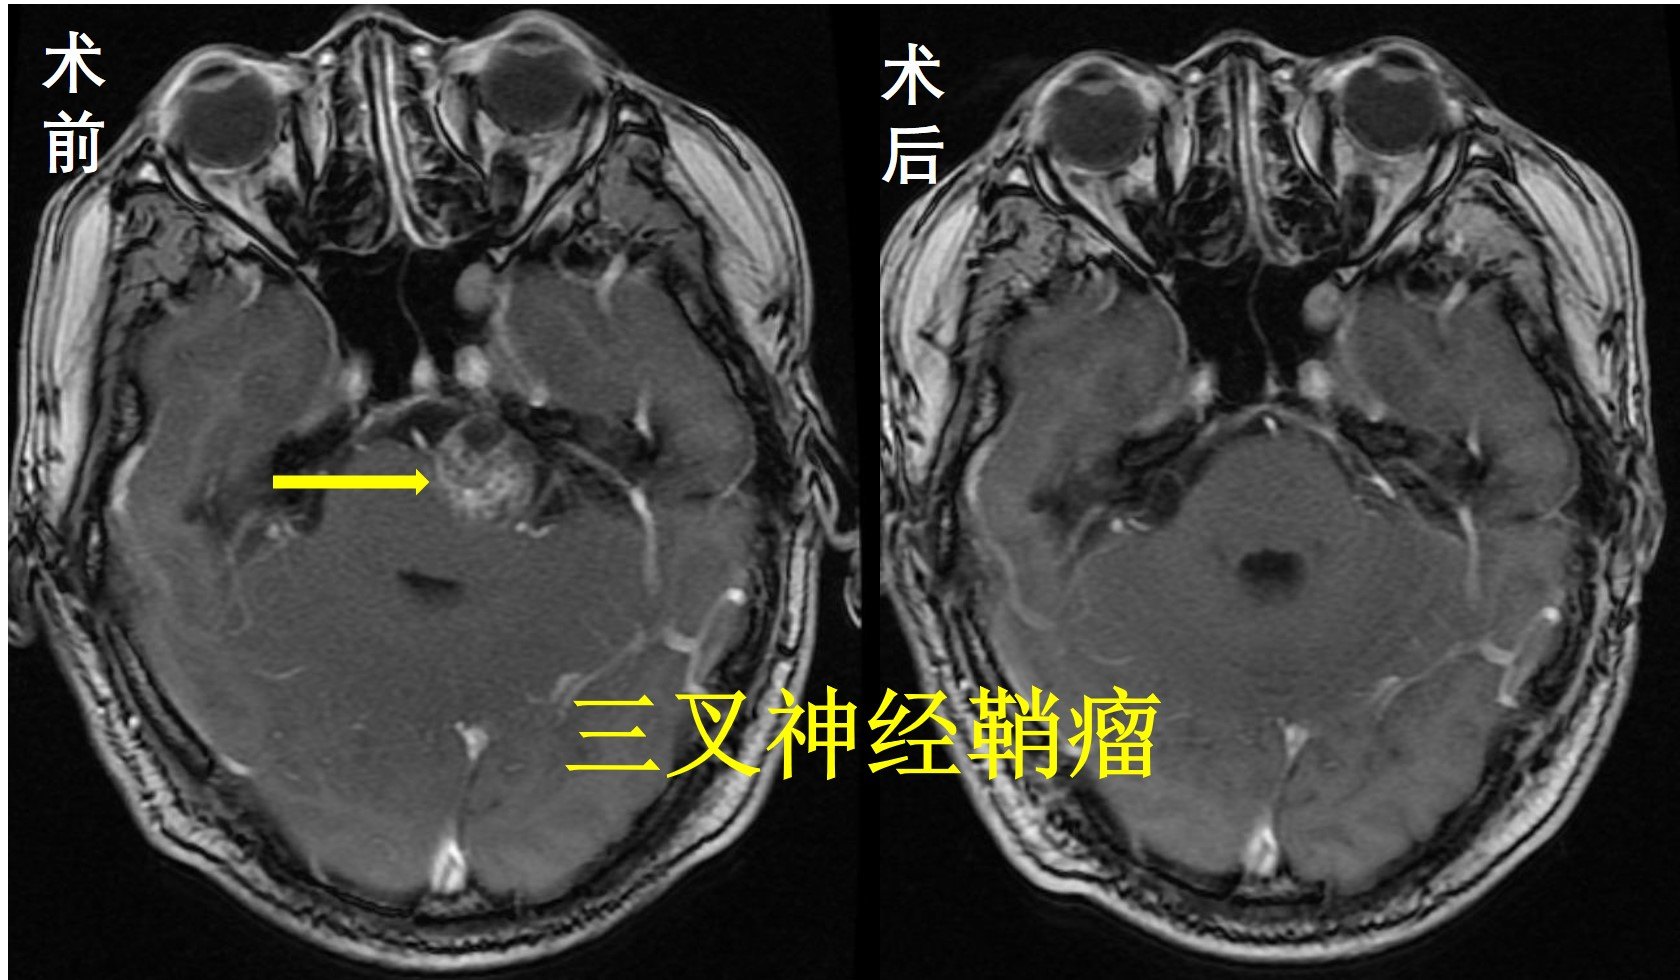

三叉神经鞘瘤

图片尺寸1080x810